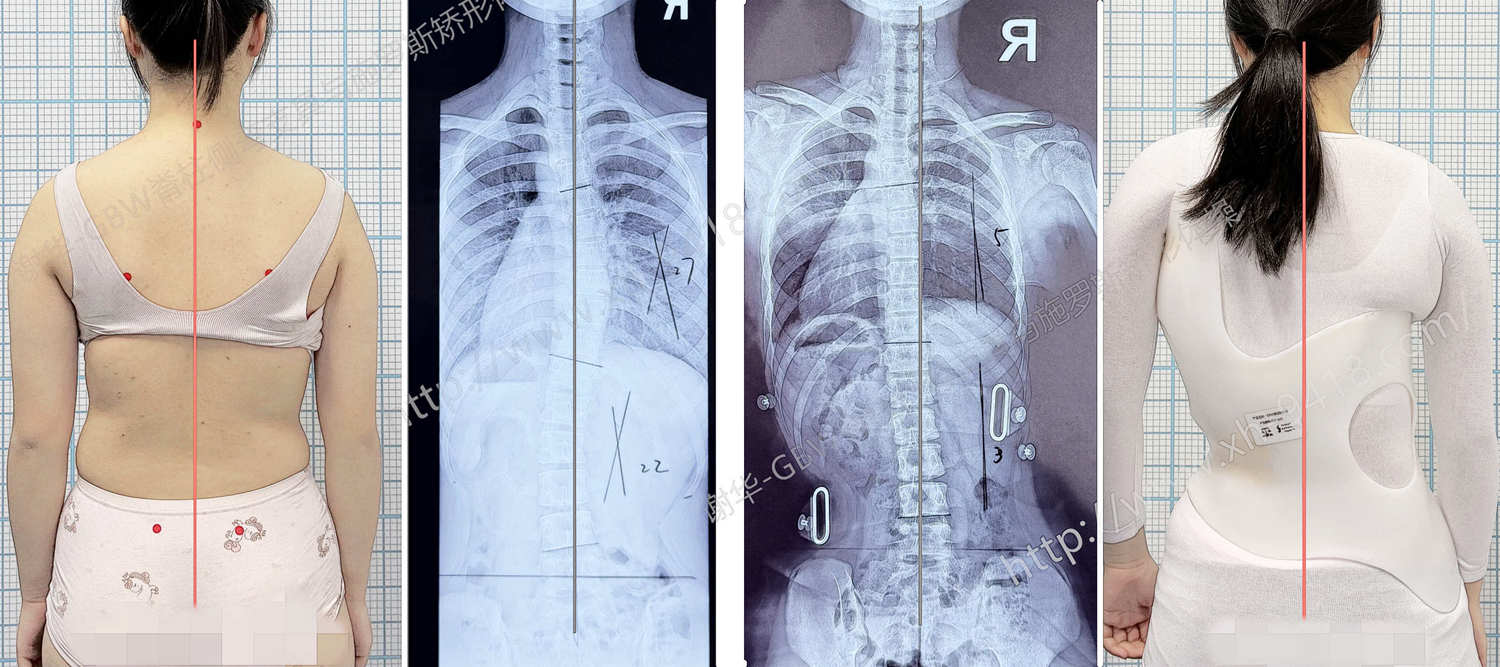

何X,女,12岁6个月。半年前发现脊柱侧弯,当时拍摄X线片显示脊柱呈 S形的侧弯曲线,Cobb角为:胸弯21°、腰弯17°。由于当时弯曲度数不大,暂时选择锻炼结合定期观察随访。

半年后复查X线片,发现侧弯曲线出现明显进展:胸弯增加至27°,腰弯增加至22°。同时骨龄评估显示 Risser征1级,提示孩子正处于生长发育的快速阶段,也是脊柱侧弯最容易进展的时期。综合评估后,建议家长为孩子定制 GBW型矫形支具 进行干预。

在家长和孩子的积极配合下,孩子坚持规范佩戴GBW支具4个月。近日来成都工作室进行复查评估:在脱支具后站立位观察,躯干体表基本恢复对称;前屈位检查时,背部剃刀背明显降低至3°。从体表姿态来看,脊柱侧弯的外观已经得到明显改善。

矫正前后对比-站立位